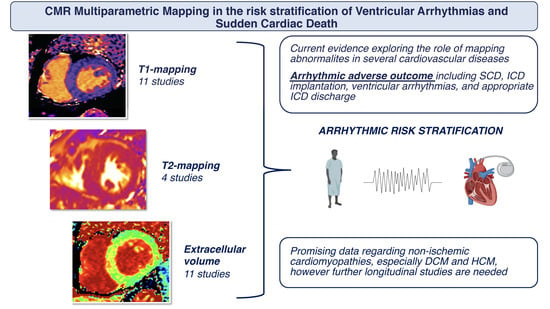

Multiparametric Mapping via Cardiovascular Magnetic Resonance in the Risk Stratification of Ventricular Arrhythmias and Sudden Cardiac Death

Abstract

:1. Introduction

2. Association of CMR Mapping Alterations and Ventricular Arrhythmias in Cardiovascular Diseases

2.1. Ischemic Heart Disease

4. Conclusions